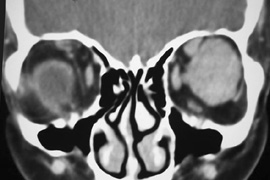

HISTORY AND PHYSICAL EXAMINATION A wide range of signs and symptoms may alert the ophthalmologist to involvement of the orbit by a pathologic process. These include proptosis or globe displacement; compressive optic neuropathy with visual field or visual acuity loss; refractive changes such as progressive hyperopia, restricted eye movements, and diplopia; optic disc changes, including pallor or edema; and fundus changes such as choroidal folds. These manifestations may be the consequences of a primary intraorbital disease or may occur secondary to involvement of the orbit by a process extending from the overlying soft tissues, periorbital sinuses, or intracranial cavity. All patients with suspected orbital pathology should have a thorough ophthalmic history and physical examination. Detailed questioning about the nature, onset, and progression of the chief complaint is necessary to formulate a differential diagnosis. Previous ocular and general medical history related to diseases, operations, medications, and family history should be obtained. A general review of systems will identify risk factors for related systemic diseases, such as hyperthyroidism, metastatic cancer, or lymphoma. A complete examination of the eye and periocular tissues is essential. Abnormal protrusion or displacement of the globe, extraocular motility disturbances, soft-tissue changes, and decreased corneal or periorbital cutaneous sensation should be specifically sought. Special attention always should be directed to evaluation of optic nerve function. Visual acuity testing alone is not sufficient because visual acuity often is preserved initially in patients with compressive optic neuropathy. All patients should be examined closely for detection of an afferent pupillary defect, abnormal color vision, or loss of contrast sensitivity. Formal perimetry should be performed to rule out peripheral field loss. If the presentation has been gradual, evaluation of old photographs may help establish the time course of the pathologic process. In selected cases, appropriate blood work to help identify orbital inflammatory or neoplastic processes also should be obtained. ORBITAL IMAGING Valuable information about the nature and extent of an orbital pathologic process is provided by imaging studies such as computed tomography (CT) scan, magnetic resonance imaging (MRI), and orbital echography. Better spatial resolution, ready accessibility, and lower cost make CT the preferred choice for orbital imaging in most cases. Orbital fat provides a natural contrast between most adjacent orbital structures on CT scanning, and orbital bones are visualized well. Computed tomography is essential for evaluation of the orbital bones because they cannot be imaged with MRI. Direct coronal or sagittal images are important to identify the relationship of a lesion to the optic nerve so that the surgical approach can be planned to avoid traversing the optic nerve (Fig. 1). Newer multislice helical CT scanners allow continuous acquisition of data so that a single rapid pass allows formatting in axial, coronal, and sagittal planes. Multislice CT provides shorter examination times with reduced motion artifact and radiation exposure when compared with conventional CT. Magnetic resonance imaging is useful in selected cases, especially when evaluating the orbital cranial junction. Significant bony artifact and a lack of orbital fat in the orbital apex make CT scan resolution of the orbital apex structures poor. Because cortical bone has low signal on MRI, there is no bone artifact when viewing the orbital apex on MRI. The lack of intervening fat in the apex to provide contrast is overcome on MRI because contrast is provided by the individual nuclear characteristics of each tissue so that the orbital apex structures are visualized well. Consequently, conditions that affect the optic nerve and chiasm, such as optic nerve meningioma and glioma, generally are evaluated with MRI rather than CT scan (Fig. 2). Use of a contrast agent such as gadolinium can further enhance the T1 signal intensity of lesions and is particularly helpful in imaging areas where there has been a breakdown in the blood–brain barrier. Because orbital fat produces a bright signal on T1-weighted images, orbital MR usually is performed with “fat suppression” to prevent masking of lesions. However, incomplete fat suppression can produce artifacts that may be misinterpreted as abnormal enhancement. A few other orbital conditions are better visualized with MRI than CT scanning.1–3 Often, organic foreign bodies, such as wood, are not imaged well with CT scan. These foreign bodies often are visible with MRI. However, care must be taken when imaging any metallic intraocular or intraorbital foreign body because the strong magnetic field of the MR scanner may cause the foreign body to shift position and damage surrounding structures. In some tumors and vascular anomalies, high blood flow is appreciated on MRI. This is caused by a lack of signal, known as a flow void, created by blood flowing rapidly through larger vessels. Tumors that originate in the brain and extend into the orbit secondarily, such as sphenoid wing meningioma, also are visualized well with MRI. However, bony detail and calcification within the meningioma are not imaged well. In unusual circumstances such as this, CT scan and MRI may prove to be complementary, and both techniques may be required to fully evaluate the orbital disease process. Orbital echography can provide useful information in the evaluation of orbital disorders. Because each tissue has its own acoustic characteristics, echography can provide a high degree of tissue contrast. Spatial resolution also is quite good. In some situations, echography can provide information not available on CT scan or MRI. These instances include detection and measurement of blood flow4 and intraoperative localization of small foreign bodies.5 Orbital echography requires specialized equipment and a large amount of expertise to obtain the detailed information that is readily available with CT scan or MRI; consequently, its use has decreased. Recent advances in orbital imaging have been summarized by Lee and colleagues.6 |